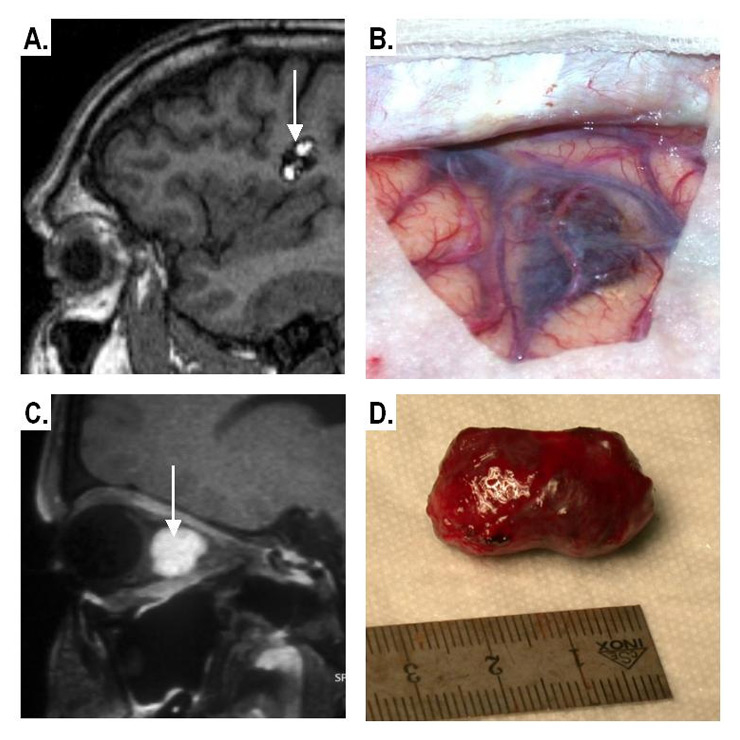

Figure 6

Imaging and gross pathological appearance of CM.

Supra-tentorial CM

A: Non-contrast T1-weighted MRI showing the typical “popcorn-like” appearance

B: Intra-operative image

Intra-orbital CM

C:Contrast-enhanced fat-suppressed MRI (well-defined enhancing intraconal mass).

D: Gross pathology of the CM after excision.

In our study, around 75% of cases were symptomatic which is in accordance with previous figures of 69–88% of cases with CMs becoming symptomatic at least once in their life [2–4]. The lesions had a supra-tentorial location in 74% in previous studies [2] and in 54.5% in our sample. Isolated infra-tentorial CMs were less common (22.15%), while spinal and orbital lesions were quite rare in our study (3% and 1.5% respectively). The MRI appearance of the orbital CMs in our series (fig. 6C,D) was similar to that described previously by Hejazi and co-workers, who suggested that orbital CMs represent a distinct clinicopathologic and neuroradiologic entity. They found that orbital CMs, in comparison with cerebral CMs, showed non-degenerated well-developed vessel walls and were covered by a hard and compact capsule. On MRI these lesions were well defined, exhibited a homogeneous MRI-signal and enhancement patterns. Calcification was rather rare [23].